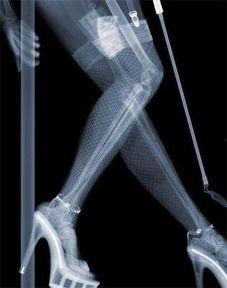

红丝袜,这个曾经只属于女性的时尚单品,如今却成为了机器人的新宠。据《时尚科技》杂志报道,近年来,越来越多的科技公司开始将红丝袜作为机器人外观设计的一部分。这种设计不仅增添了科技产品的时尚感,也让机器人看起来更加亲切。

红丝袜的材质柔软,颜色鲜艳,与机器人的金属质感形成鲜明对比。这种独特的视觉效果,让人不禁对这款机器人产生好奇。而红丝袜的弹性,也让机器人能够更好地适应各种场合,无论是正式的商务场合,还是轻松的休闲时光,都能展现出独特的风采。